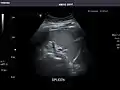

Spleen

Spleen: Normal in size.